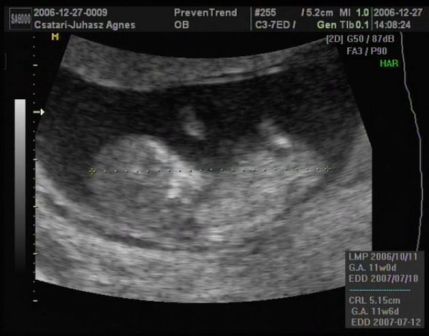

...Szerettem volna veletek megosztani, hogy hogy ficánkolt a drágám, de ilyen rossz hir után most képtelen vagyok!

A lényeg, hogy minden rendben van, és hogy uh szerint még nagyobb is egy héttel! Hallottam kalapálni a kis szivét, láttam a kezecskéit és a lábait...

A nyaki redőnk 0.7 vagyis tökéletes.

Január 23-án megyek a következő vérvételre az integrált teszt miatt!

Van dvd a kicsimről, csináltam nektek belőle képeket:

Kép Kép Kép Kép

Ági, köszönjük a képeket, nagyon jók lettek – szuper! Még a köldökzsinor is látszik :D és, még az is, ahogy a kezecskéit mozgatja.... jéééééé

Áááááááááági!!! Ez egyszerűen egy tökéletes bébike!!! És hogy már milyen nagy baba! Hihetetlen, hogy meg van mindene!!! Hol voltál 3D-s UH-n? Az integrált tesztet majd alkalomadtán meg fogom tőled kérdezni, mert most én is tervezek majd menni. Mindent meg akarok tenni a megnyugvásomért! Remélem, most már maximálisan nyugodt vagy a kis bébit illetően!

Amugy a Bolgárkerék utcában voltam integrált teszten. Ha jól tudom még Juci is ott volt. Isten igazából nem is a 3D-s volt a nagy része a vizsgálatnak, hanem, hogy a Down-kór szűrés. És az egészben az a jó, hogy pont az én dokibácsim van ott az uh-on! :) Mindent megmért, a combcsonttól kezdve a pulzust, az orrcsontot, a fejét... A 3D-sből ennyit csinált amit láttok. Majd késöbb elmegyek mégegyszer, amikor majd a szivét is jól látni, és akkor is csináltatok dvd-t.

Ez egyszerűen csodálatos volt! Úgy mozgolódott, sőt a látjátok a méhem milyen alakú... A drágám feljebb ugrált és onnan "csúszdázott le" (a doki ezt a szót használta). Csodálatos volt látni mindent. Sőt a doki még azt is megnézte, hogy mi van a lába között... Azt mondta csak tipp, és hogy ne vegyük készpénznek, de mintha lenne valami a lába között :D ...azért én még reménykedek,hogy kiscsaj, mert megnéztem a könyvben (csodálatos utazásban), hogy ilyenkor még a lányoknak is kitüremkedik, és nem lehet igazán megkülönböztetni! :roll: :lol:

És igen, kicsit megnyugodtam. Bár egy mondat megmaradt bennem és tudom, hogy azt fogom várni majd a következő uh-on: "gyomor és hólyag telítődése jelenleg nem ábrázolódik" De szerintem ehhez még kicsik is vagyunk... :(